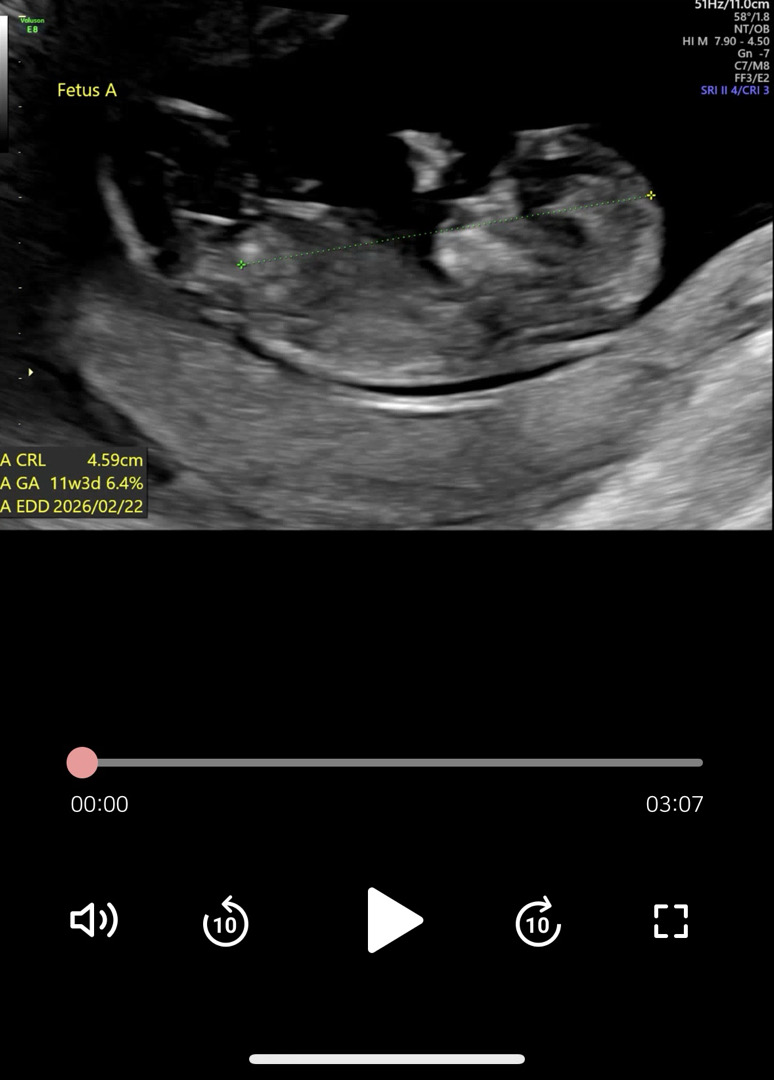

11주6일차 각도법 봐주세요🤍일란성

쌍둥이입니다🥹